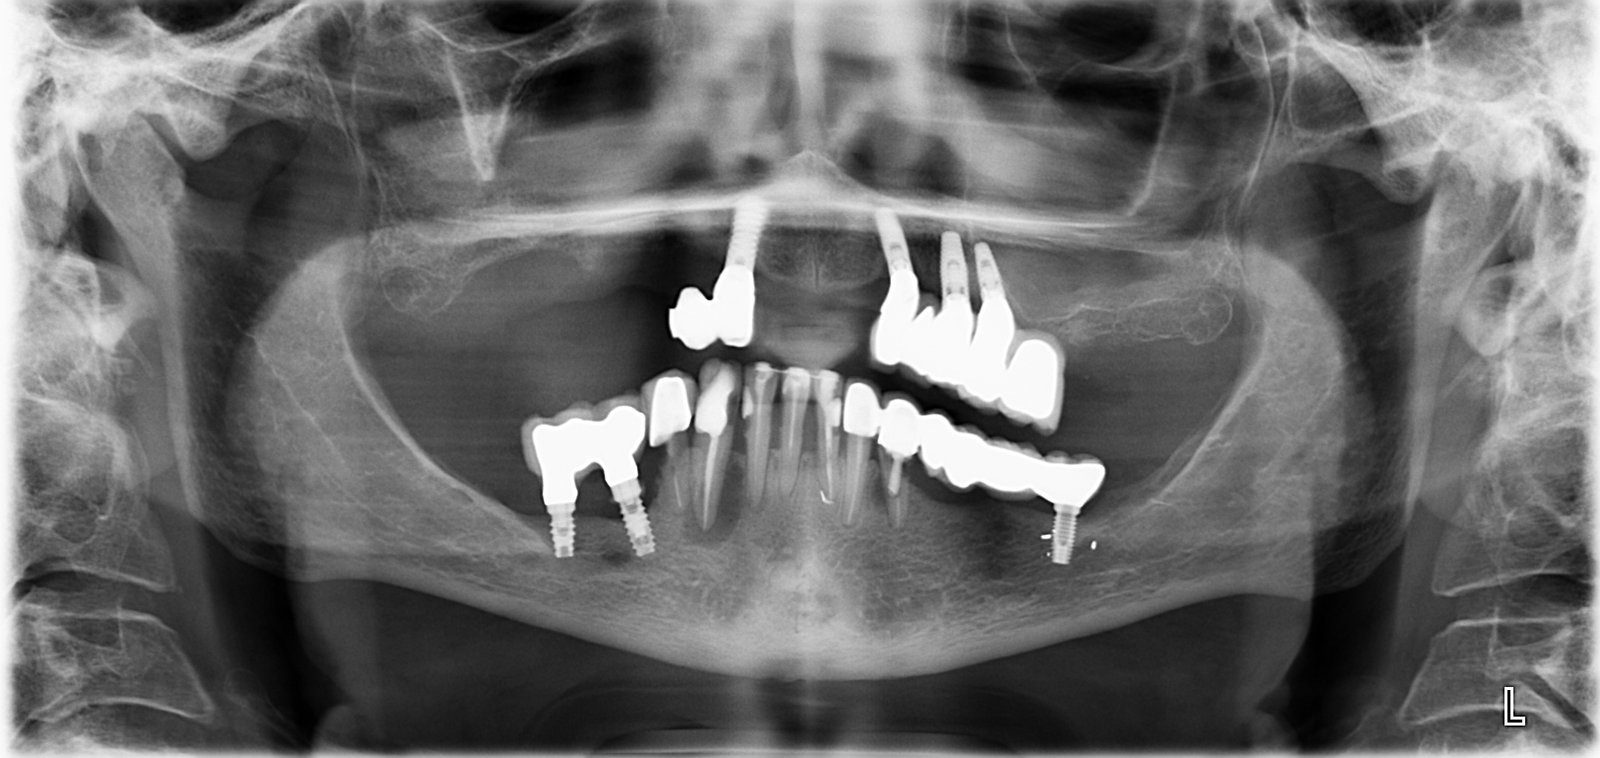

Buenos días. Muchas gracias por vuestra web, es muy interesante. Me estreno por fin en ella tras varias recomendaciones de amigos. Os envío la ortopantomografía de 3 implantes de mandíbula [...]